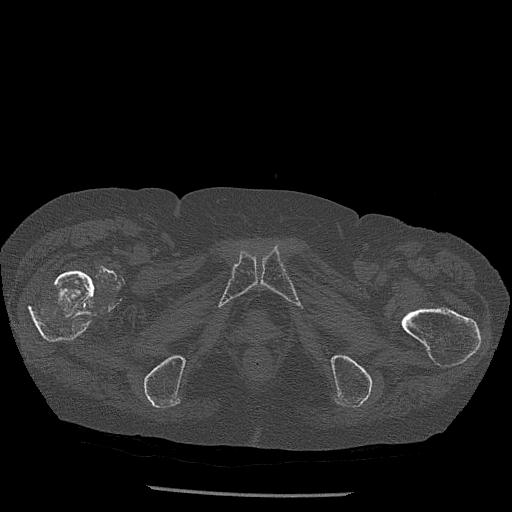

110286 2/17 股関節 2R 74歳女性 右人工骨頭

102903 股関節 2R 1/28 +股関節 2R 1/29 78歳女性 左人工骨頭

82084 1/14 1/20 股関節 2R 78歳男性 右人工骨頭

91569 3/25 両股正面とラウエン 70歳女性 人工骨頭+バンクーバー